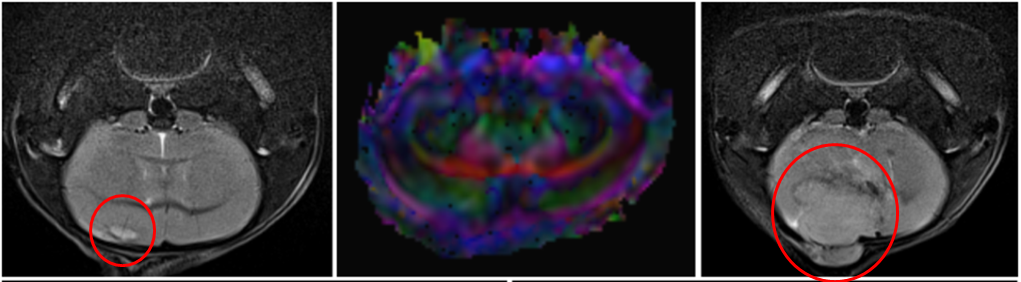

Tumorwachstum im Mausmodell (links 2 Wochen nach Injektion, rechts 6 Wochen nach Injektion).